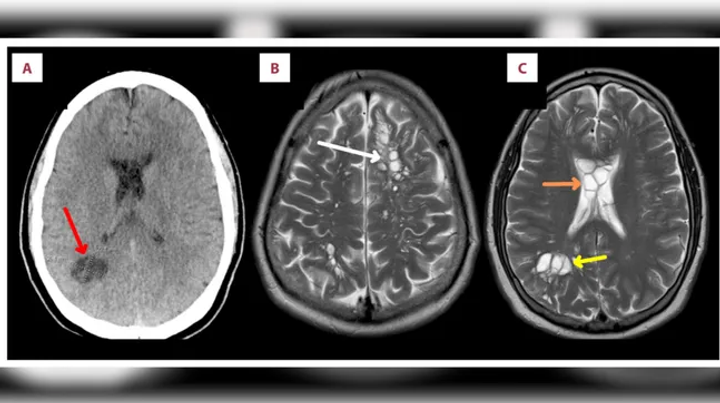

Dia lalu pergi ke klinik. Di sana hasil computed tomography (CT) scan mengungkapkan bahwa pria itu memiliki banyak kista di otaknyaโterutama di bagian saraf yang terletak jauh di dalam organ. Ditemukan pula beberapa kista di sudut kanan bawah otaknya. Karena kondisinya mengkhawatirkan, dokter lantas merujuk pasien ke rumah sakit.

Di RS, pemindaian magnetic resonance imaging (MRI) menemukan adanya kista di bagian depan dan tengah lapisan luar otak pasien, serta pembengkakan. Pria itu didiagnosis mengalami neurocysticercosis yang diakibatkan oleh infeksi larva Taenia solium, cacing pita yang bisa menginfeksi babi.